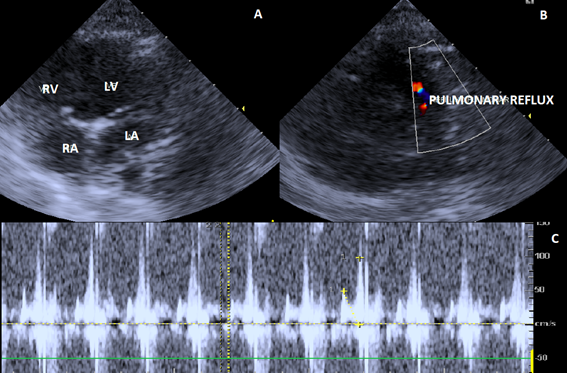

The echodoplercardiogram showed changes in the tricuspid (Figure 2), mitral (Figure 3) and pulmonary (Figure 4) valves. Due to the presence of pulmonary artery pressure greater than 25-30mmHg (35 mmHg), a diagnosis of pulmonary hypertension was definided.

Figure 4 Echocardiographic image showing right parasternal short-axis view of the pulmonary valve. A. Pulmonary valve with normal appearance and movement of its valves. B. Doppler study and color flow mapping showing mild valve regurgitation. C. Spectral doppler tracing with pulmonary valve regurgitation.